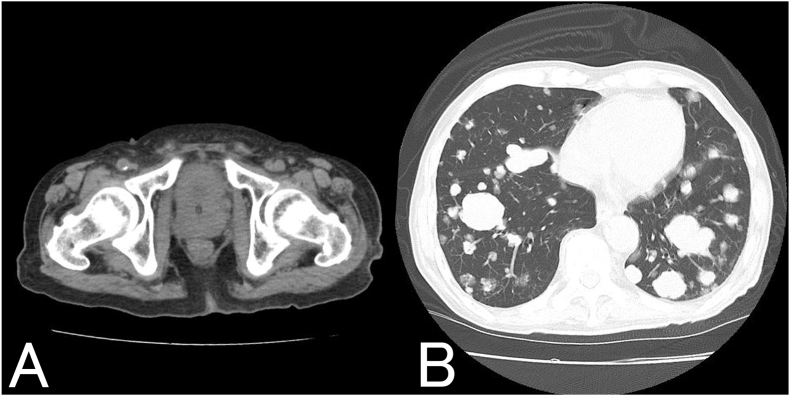

我们报告的情况下,85岁的男子诊断为转移性前列腺癌三年前。在联合雄激素阻断治疗期间,他出现了血尿、便血和疲劳。这些症状归因于前列腺癌的局部进展和不适当的抗利尿激素分泌综合征(SIADH)。限水、姑息性放疗和托伐普坦均可缓解症状。4个月后,由于高钙血症,他出现食欲不振和疲劳,最终被诊断为恶性体液性高钙血症(HHM)。

We report the case of an 85-year-old man diagnosed with metastatic prostate cancer three years earlier. While on combined androgen blockade, he developed hematuria, hematochezia, and fatigue. These symptoms were attributed to local progression of prostate cancer and syndrome of inappropriate antidiuretic hormone secretion (SIADH). Water restriction, palliative radiation, and tolvaptan alleviated the symptoms. Four months later, he experienced appetite loss and fatigue due to hypercalcemia, ultimately leading to a diagnosis of humoral hypercalcemia of malignancy (HHM).